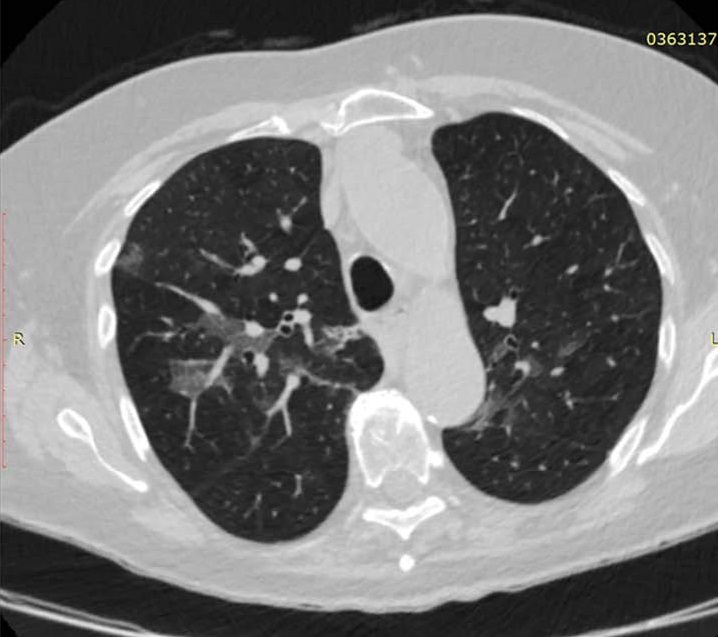

• the computed tomography system 64-slice manufactured by NIPK Electron Co. for primary assessment and differential diagnostics of chest diseases, as well as for revealing concomitant diseases. The modular CT unit can be equipped with a computed tomography system with another slice number as an option. According to the interim methodological guidelines “Prevention, Diagnostics, and Treatment of a new Coronavirus Infection” developed by the Ministry of Health of Russia, a CT scan is considered one of the basic methods of COVID-19 diagnosis.

The computed tomography system 64-slice (CT) installed in the module unit is equipped with a wide set of specialized software applications for diagnostic imaging in patients with respiratory disorders, vascular abnormalities, cancer, as well as for assessment of cerebral, renal, and hepatic blood supply. Thanks to this, CT is in high demand not only during the COVID-19 pandemic.